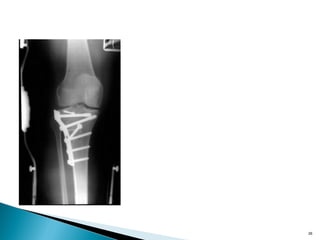

•Resist axial load by applying force at 90 degree to the axis of

•Metaphyseal tibial plateau split fractures

• Used when the fracture will only displace in one direction

• Only useful in metaphyseal fractures

• Applied so as to resist one deforming force

•Resist axial loadby applying force at 90 degree to the axis of potential deformity •Metaphyseal tibial plateau split fractures 24

• Used whenthe fracture will only displace in one direction • Only useful in metaphyseal fractures • Applied so as to resist one deforming force 25